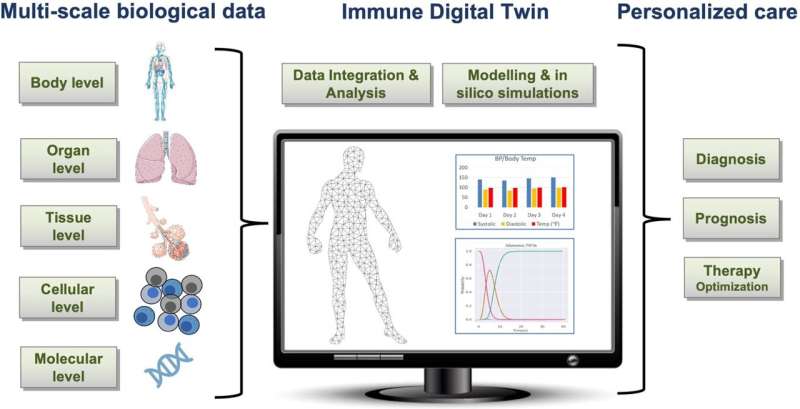

《Nature》细胞自杀的新诱因

埃默里大学(Emory University)的研究人员发现了一种皮肤细胞死亡的机制,这可能最终导致新的治疗方法,用于治疗“食肉性”感染、脱发、荨麻疹,甚至可能是最致命的皮肤癌——黑素瘤。

拉洛克说,这项研究显示,他的团队发现的一种名为gasdermin A的蛋白质会诱导人体最大器官皮肤的细胞死亡。他说,正是这种蛋白质,通过召唤更多的免疫细胞到达这个部位,起到了抵御细菌攻击的早期预警系统的作用。

身体依靠细胞死亡来保持健康——尽管这一过程也可能意外地引发损害。然而,到目前为止,人们对这一过程的机理还知之甚少。这项新发现推进了对细胞死亡的科学理解,因为它阐明了皮肤中引发细胞死亡的原因。

拉洛克说,他们在研究中发现的新的免疫蛋白gasdermin A,可能不仅在保护GAS,也在其他病原体中发挥重要作用。“我们正在研究如何利用我们的发现来靶向细胞死亡,以帮助我们更好地治疗感染,以及脱发、皮炎、银屑病和瘢痕疙瘩等疾病,因为这些都涉及到皮肤细胞死亡。”